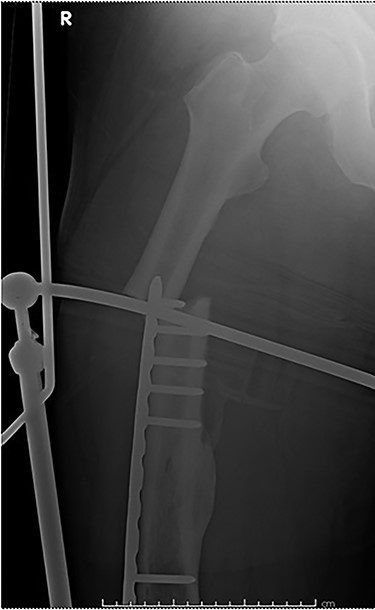

The cases of failure are here examined in more detail. Case 1 (Figs 1 and 2): this active gentleman was paddleboarding off the Llŷn peninsula when he was knocked onto his side by a wave.

Fracture above plate tip following successful union for Case 1.

Clearly, this has occurred following on from successful union. Despite a sound original fixation, the rigid construct has acted as a lever-arm to produce a fracture above the plate tip. In long spiral fracture configurations such as this, antegrade intra-medullary nailing could be considered as the primary treatment modality.